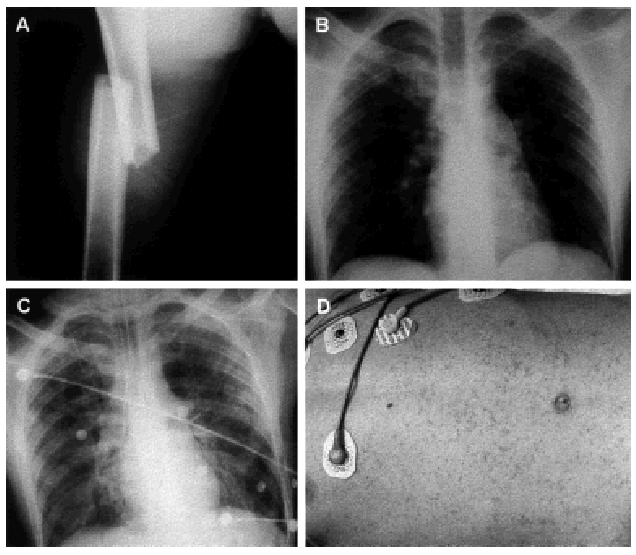

Varón de 18 años que ingresó por una fractura del fémur derecho con acabalgamiento a consecuencia de un accidente de tráfico (fig. 1A). En el momento del ingreso, la radiografía de tórax fue normal (fig. 1B). A las 3 h del accidente, el paciente comenzó con agitación seguida de coma y taquipnea con cianosis. Una nueva radiografía de tórax mostró infiltrados alveolares bilaterales (fig. 1C) y la exploración cutánea reveló un exantema petequial diseminado toracoabdominal (fig. 1D). Puesto que hubo una relación PaO2/FiO2 < 100, el paciente fue intubado y conectado a ventilación mecánica con FiO2 de 1 y PEEP + 10 cmH2O. El enfermo tuvo una evolución favorable, aunque presentó alteraciones de la conducta durante 2 meses. El diagnóstico fue embolia grasa con edema pulmonar y petequias diseminadas.

Figura 1.